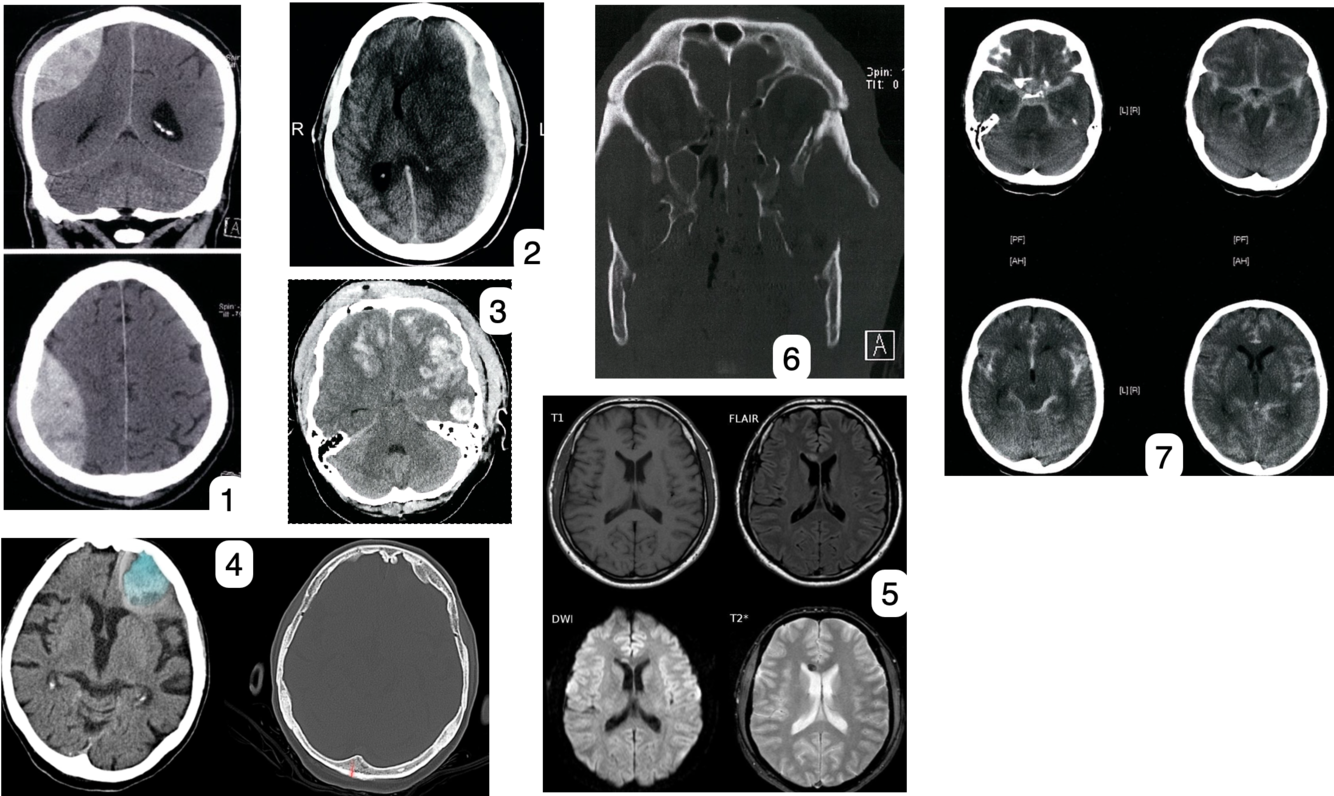

8

1. Saignement Epidurale

2. Saignement sous dural

3. Saignement intracérébral

4. Blessure coup-contre coup → fracture occi et contusion frontal

5. Lésion axonale diffuse

6. Facial et orbital fracture

7. Saignement sous arachnoïdien